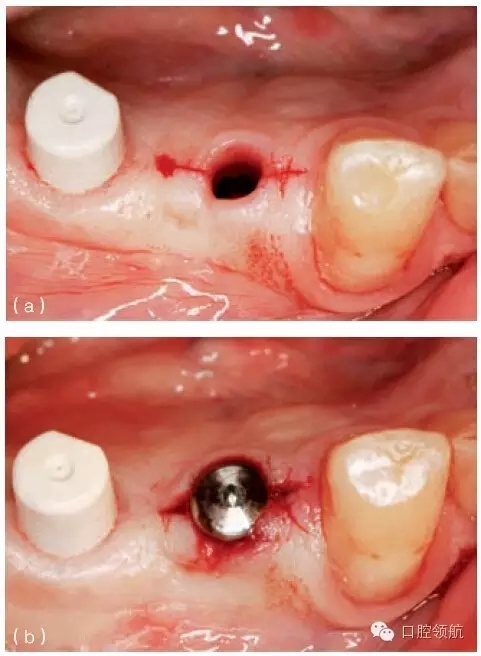

另外一個方面,深的袖口將妨礙修復(fù)體完全就位(圖9.26)。通??梢酝ㄟ^放射學(xué)檢查,確認(rèn)修復(fù)部件的就位情況,包括種植體與基臺的連接部分。即使是內(nèi)連接,轉(zhuǎn)移體或者其他修復(fù)部件也會因深袖口而不能就位。以下技術(shù)可以用于解決這些問題:可以在局部麻醉下,插入喇叭狀或者外展的基臺,以非手術(shù)的方式擴(kuò)大袖口(圖9.27 a,b),然后再通過放射學(xué)檢查確定部件的完全就位。組織會受壓發(fā)白,15分鐘后,軟組織將會擴(kuò)張,以允許理想修復(fù)部件的就位,這樣治療將得以繼續(xù)。有時,需要在鄰面做兩個小切口,以緩解袖口軟組織張力(圖9.28 a,b)。通常不需要縫合。一旦袖口組織塑形完成,可運用最佳塑形的臨時(圖9.29)或最終部件(圖9.30),來維持理想的軟組織外形。

圖9.27 (a)種植體植入時,使用窄頸的愈合基臺。(b)二期暴露時,可以采用寬頸愈合基臺,拓展袖口以適應(yīng)修復(fù)的需要。

圖9.28 (a)做鄰面切口,使軟組織易于擴(kuò)張,以適應(yīng)外展的愈合基臺。(b)寬頸愈合帽就位,阻力很小。